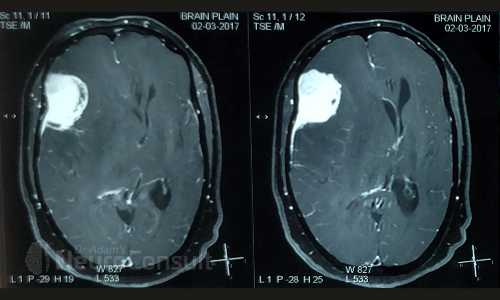

My Cases Studies & Work